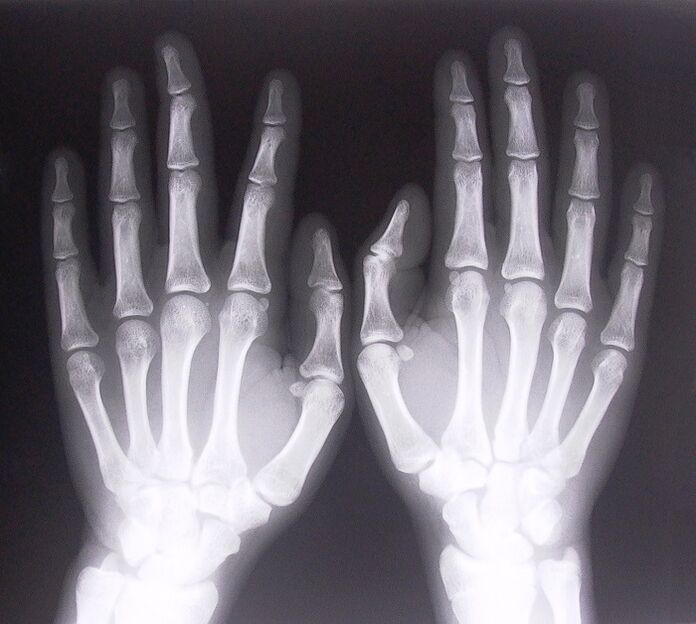

Iji malite ịgwọ mgbu nkwonkwo na mkpịsị aka, ịkwesịrị ikpebi nke ọma ọrịa kpatara ha. Iji chọpụta ụdị ọrịa na-akpagbu onye na-enwe mgbu na nkwonkwo mgbe ọ na-ehulata ogwe aka ha, ndị dọkịta na-akwado ịme usoro ndị a:

- Were x-ray.